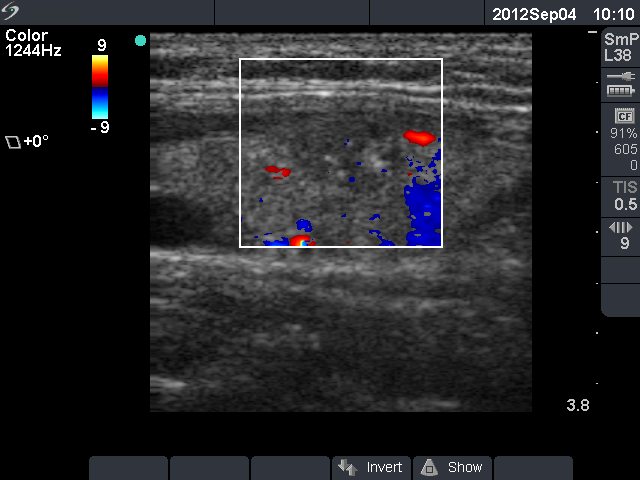

Papillary carcinoma - Case 37. (ultrasonographic picture 6)

Left lobe, longitudinal scan, color Doppler mode. A type 1 vascular pattern, i.e. neither perinodular nor intranodular blood flow is detected.